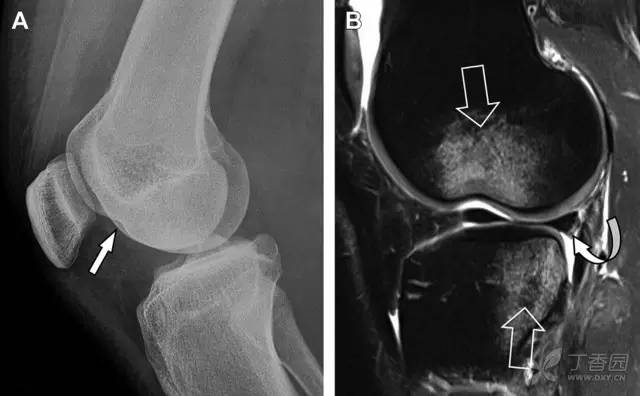

15 腓骨头撕脱性骨折膝关节外侧由髂胫束、股二头肌和肌腱、外侧关节囊韧带及外侧副韧带组成。外侧副韧带对抗过度内旋暴力,维持膝关节稳定。当内旋暴力足够大时,韧带断裂或腓骨头撕脱性骨折就发生了。在 X 线片上,骨折线垂直于股骨头外侧(图 8)。

图 8 过度伸展引起的腓骨头撕脱性骨折

A 侧位片示腓骨头外侧的垂直骨折(箭头)。B MRI 冠状位 T1 加权像示骨折碎片同时附着于外侧副韧带(箭头)和弓状韧带上(弧形箭头)。